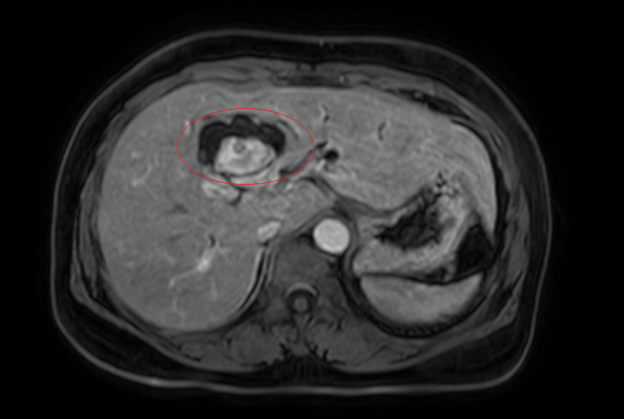

Hình ảnh giãn khu trú đường mật gan trái, tạo cấu trúc dạng nang và sỏi đường mật bên trong (vòng tròn đỏ), chèn ép kèm giãn đường mật trong gan hai bên trên phim chụp MRI